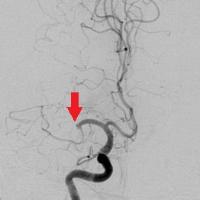

脳動脈瘤塞栓術

脳動脈瘤が破裂して出血するのを防ぐために、脳動脈瘤にコイルを詰めて血液が入り込まないようにする手術です。

術後に血管撮影を行うと、コイルで置き換わった脳動脈瘤は造影剤が入らないため描出されなくなります。